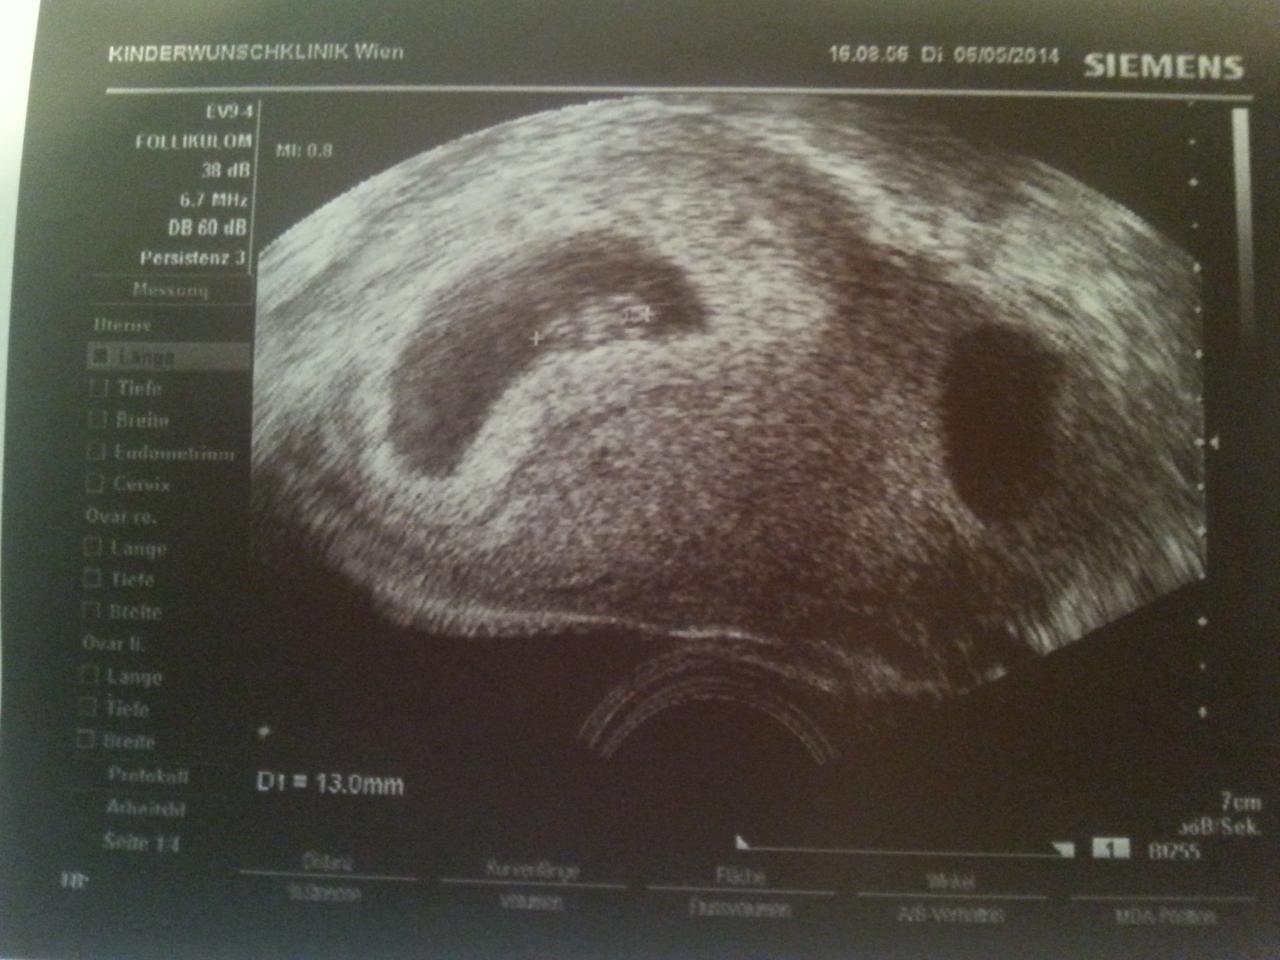

Anbei die bilder :-D